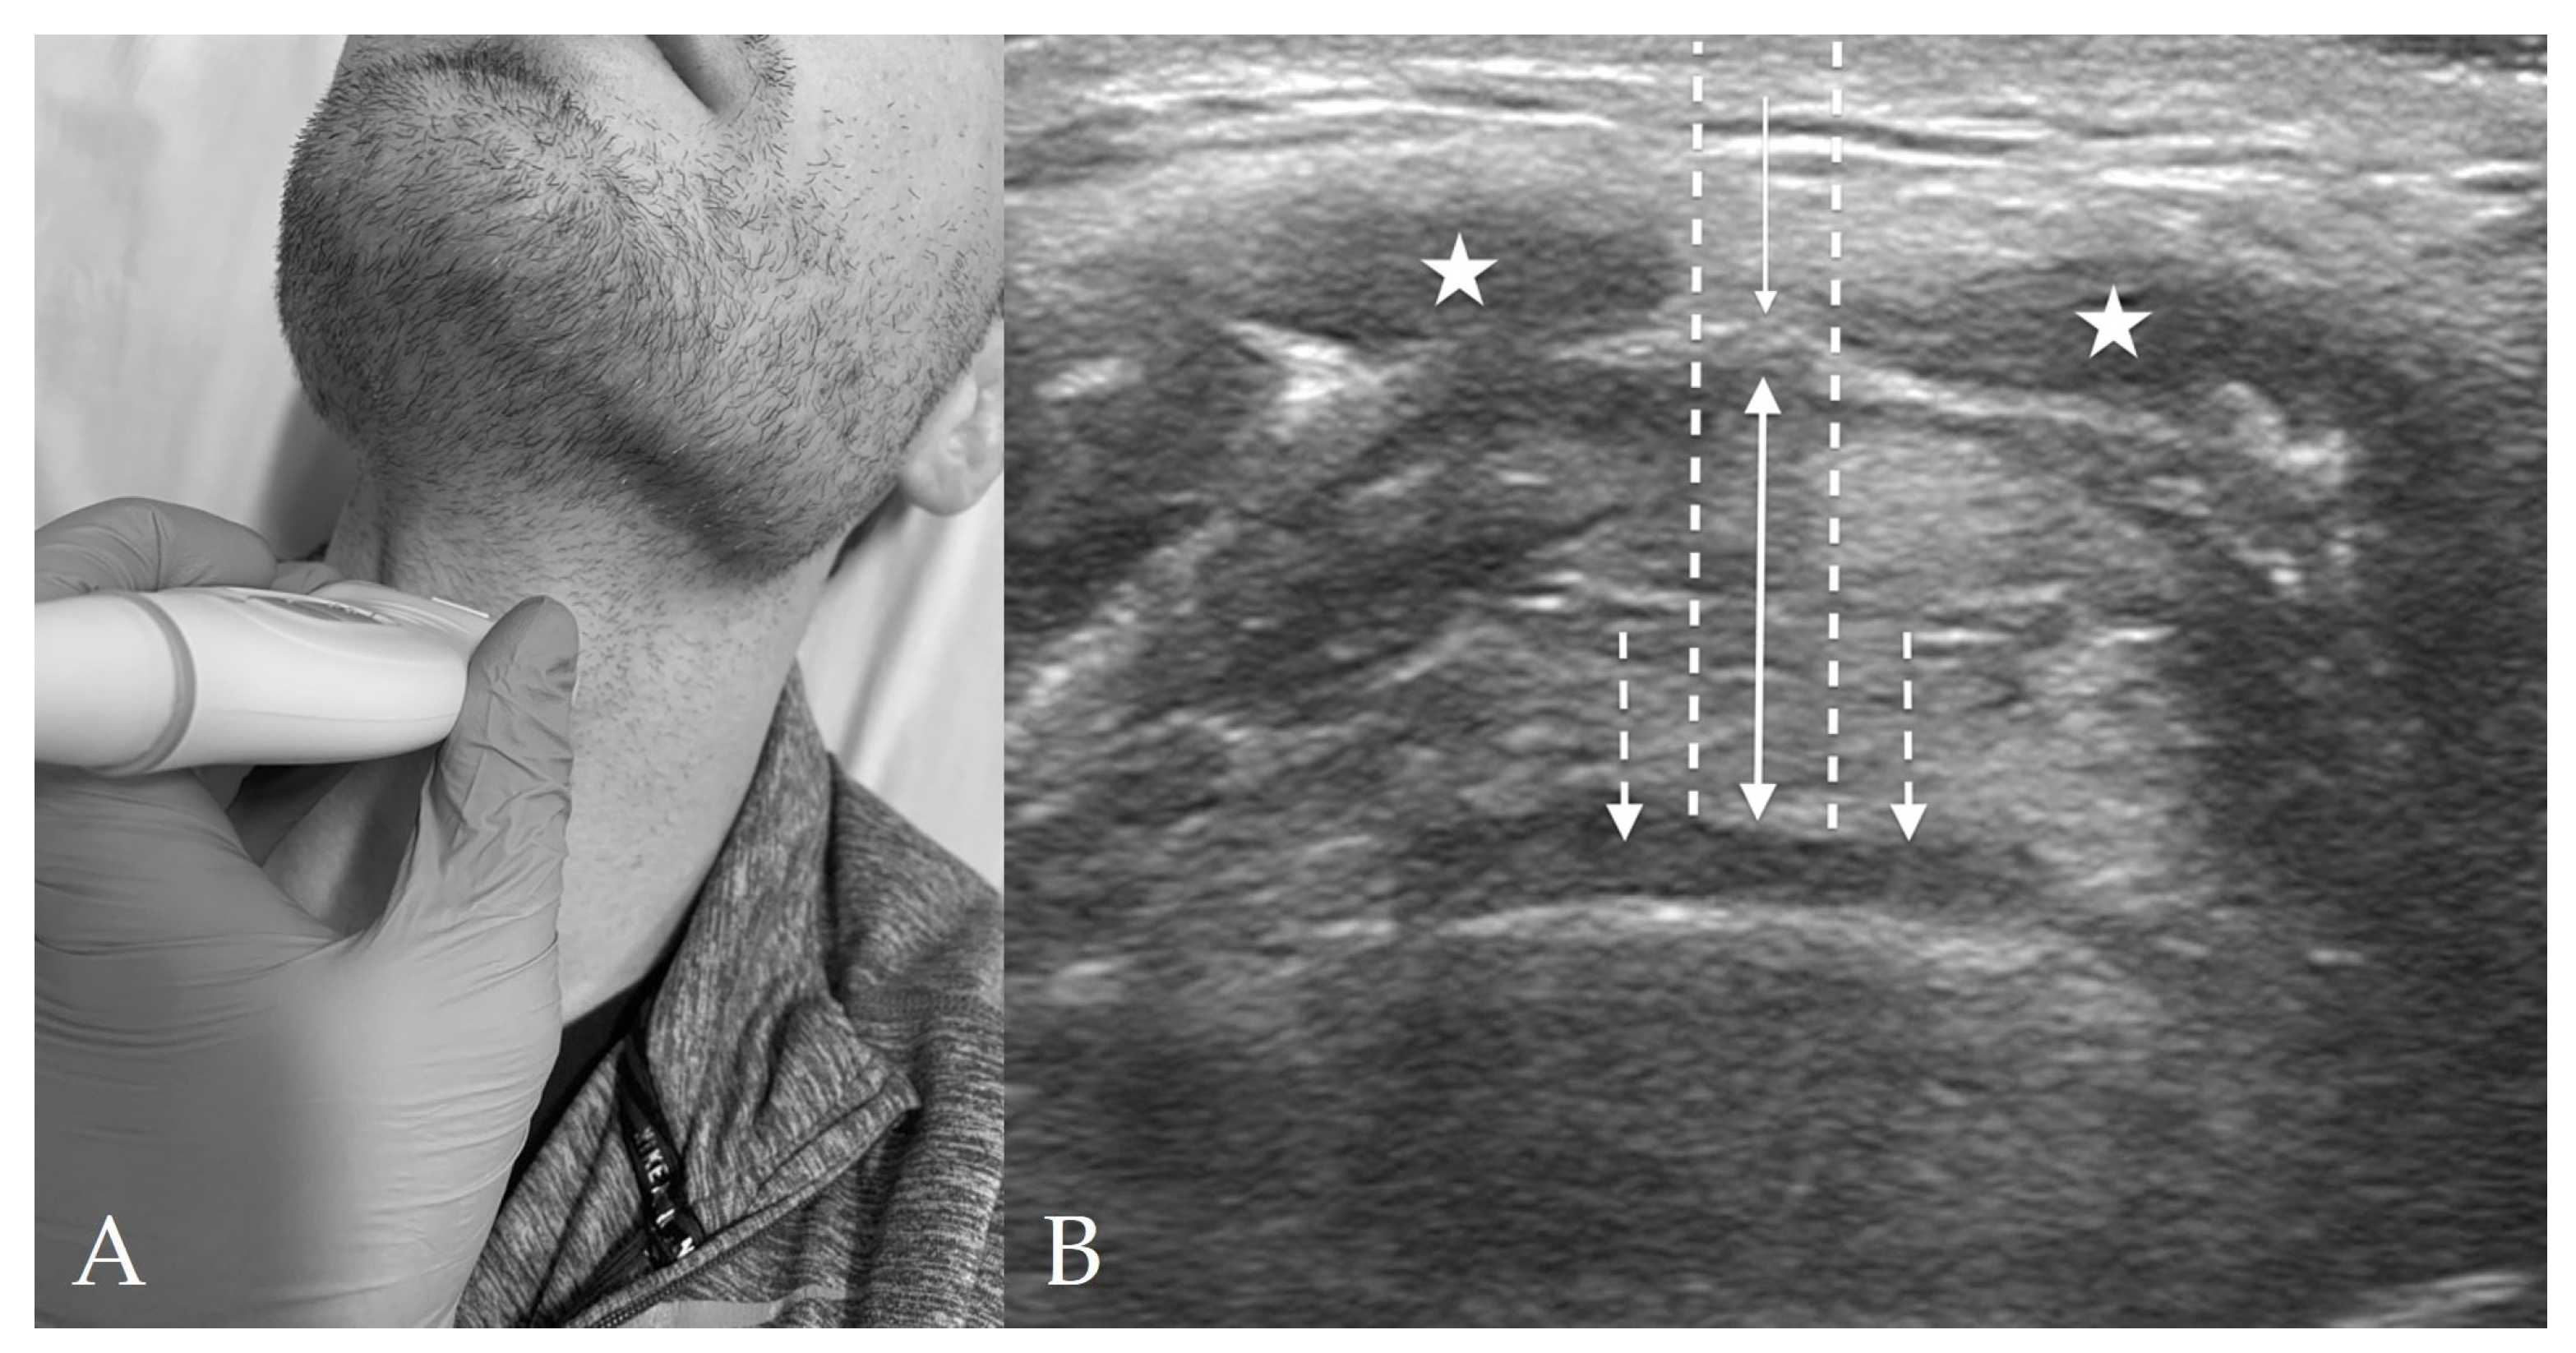

4.3. Thyroid View

8. Preparation for Cricothyrotomy

- Kristensen, M.S.; Teoh, W.H.; Rudolph, S.S. Ultrasonographic identification of the cricothyroid membrane: Best evidence, techniques, and clinical impact. Br. J. Anaesth. 2016, 117 (Suppl. S1), i39–i48. [Google Scholar] [CrossRef] [PubMed]

- Rai, Y.; You-Ten, E.; Zasso, F.; de Castro, C.; Ye, X.Y.; Siddiqui, N. The role of ultrasound in front-of-neck access for cricothyroid membrane identification: A systematic review. J. Crit. Care 2020, 60, 161–168. [Google Scholar] [CrossRef]

- Hung, K.C.; Chen, I.W.; Lin, C.M.; Sun, C.K. Comparison between ultrasound-guided and digital palpation techniques for identification of the cricothyroid membrane: A meta-analysis. Br. J. Anaesth. 2021, 126, e9–e11. [Google Scholar] [CrossRef] [PubMed]

- Kristensen, M.S.; Teoh, W.H.; Rudolph, S.S.; Hesselfeldt, R.; Børglum, J.; Tvede, M.F. A randomised cross-over comparison of the transverse and longitudinal techniques for ultrasound-guided identification of the cricothyroid membrane in morbidly obese subjects. Anaesthesia 2016, 71, 675–683. [Google Scholar] [CrossRef]

- Nicholls, S.E.; Sweeney, T.W.; Ferre, R.M.; Strout, T.D. Bedside sonography by emergency physicians for the rapid identification of landmarks relevant to cricothyrotomy. Am. J. Emerg. Med. 2008, 26, 852–856. [Google Scholar] [CrossRef]